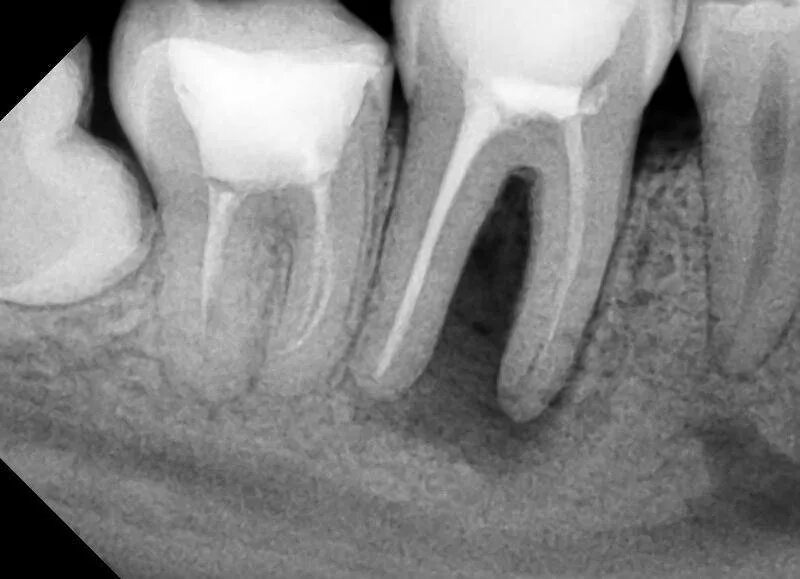

Давление под зубом